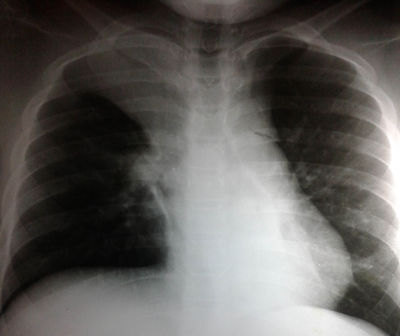

Al paciente se lo conecta a AVM modo VCV, se solicita Rx de tórax. ¿Que observa en la RX de tórax?

Answer

• Atelectasia de vértice del pulmón derecho

• NAC del vértice del pulmón derecho

• Empiema a nivel de vértice de pulmón derecho